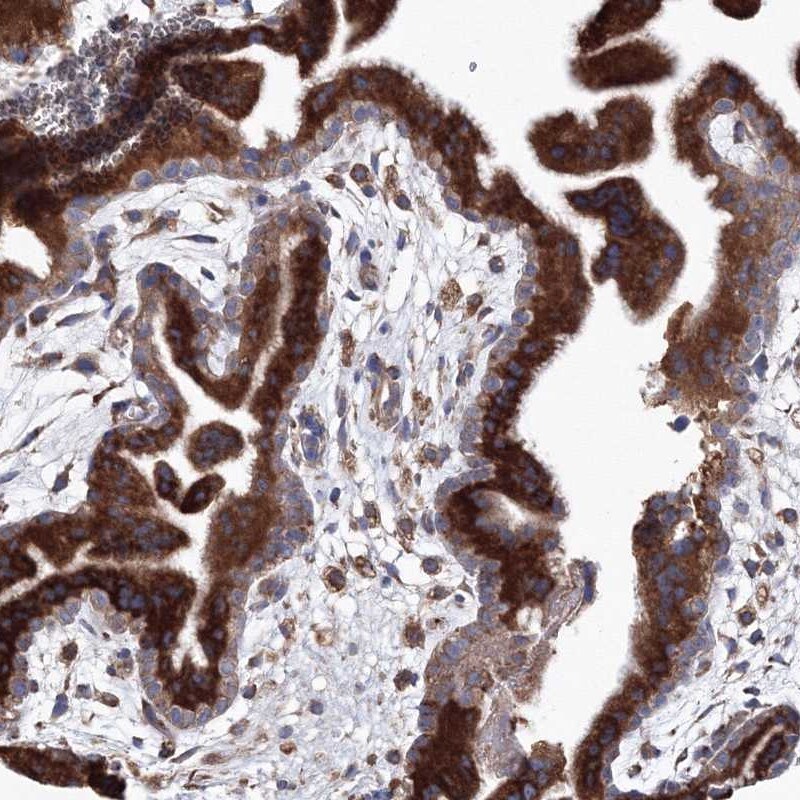

- Immunohistochemical analysis of VPS8 in human placenta using VPS8 Polyclonal Antibody (Product # PA5-57855) shows strong cytoplasmic positivity in trophoblastic cells.